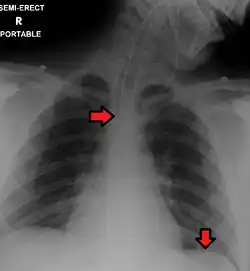

Great care must be taken to ensure that the tube has not passed through the larynx into the trachea and down into the bronchi. The reliable method is to aspirate some fluid from the tube with a syringe. This fluid is then tested with pH paper (note not litmus paper) to determine the acidity of the fluid. If the pH is 4 or below then the tube is in the correct position. If this is not possible then correct verification of tube position is obtained with an X-ray of the chest/abdomen. This is the most reliable means of ensuring proper placement of an NG tube.[10] The use of a chest x-ray to confirm position is the expected standard in the UK, with Dr/ physician review and confirmation. Future techniques may include measuring the concentration of enzymes such as trypsin, pepsin, and bilirubin to confirm the correct placement of the NG tube. As enzyme testing becomes more practical, allowing measurements to be taken quickly and cheaply at the bedside, this technique may be used in combination with pH testing as an effective, less harmful replacement of X-ray confirmation.[11] Ultrasonography alone is not sufficient to confirm position for gastric tube.[12] If the tube is to remain in place then a tube position check is recommended before each feed and at least once per day.